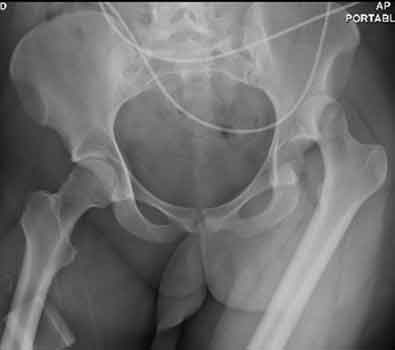

- Posterior dislocation accounts for more than 90% of all hip dislocations.

- There are four radiographic features of a posterior hip dislocation:

- Femoral head lateral and superior to the acetabulum.

- Fracture of the posterior rim of the acetabulum in most cases.

- Femur in internal rotation and adduction.

- Affected femoral head may appear smaller secondary to magnification.